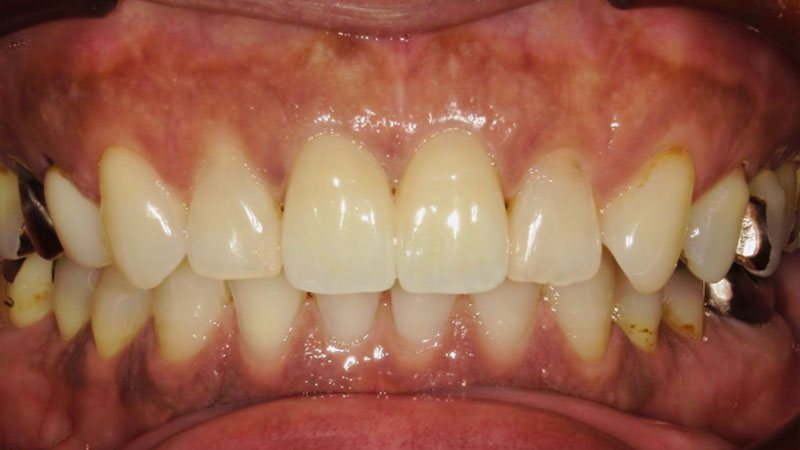

セラミックブリッジ症例

セラミック治療の症例をご紹介します。

前歯2本は抜歯し、セラミックのブリッジにされました。

今回は左上2番目は被蓋(噛み合わせが上下逆だったためブリッジを作製する際に正常被蓋にてセラミックを作製しています。

今回のように重度の歯周病の方はしっかりと歯周病治療をした上で長期的に安定する治療をさせていただいております。

患者さんもしっかり噛むことができ、審美性も改善されて大変満足されていました。

セラミックのメリットは色調再現性が高く、二次虫歯、歯周病が進行しにくくなります。

変色もほぼありません。

デメリットは保険外診療のため費用がかかること、金属を使っていないため割れる可能性があることです。

| 患者様 | 60代女性 |

|---|---|

| 主訴 | 歯の揺れが気になる |

| 治療費 | ジルコニアセラミッククラウン6本分:798,600円(税込) |

| 治療期間 | 1ヶ月 通院回数:4回 |